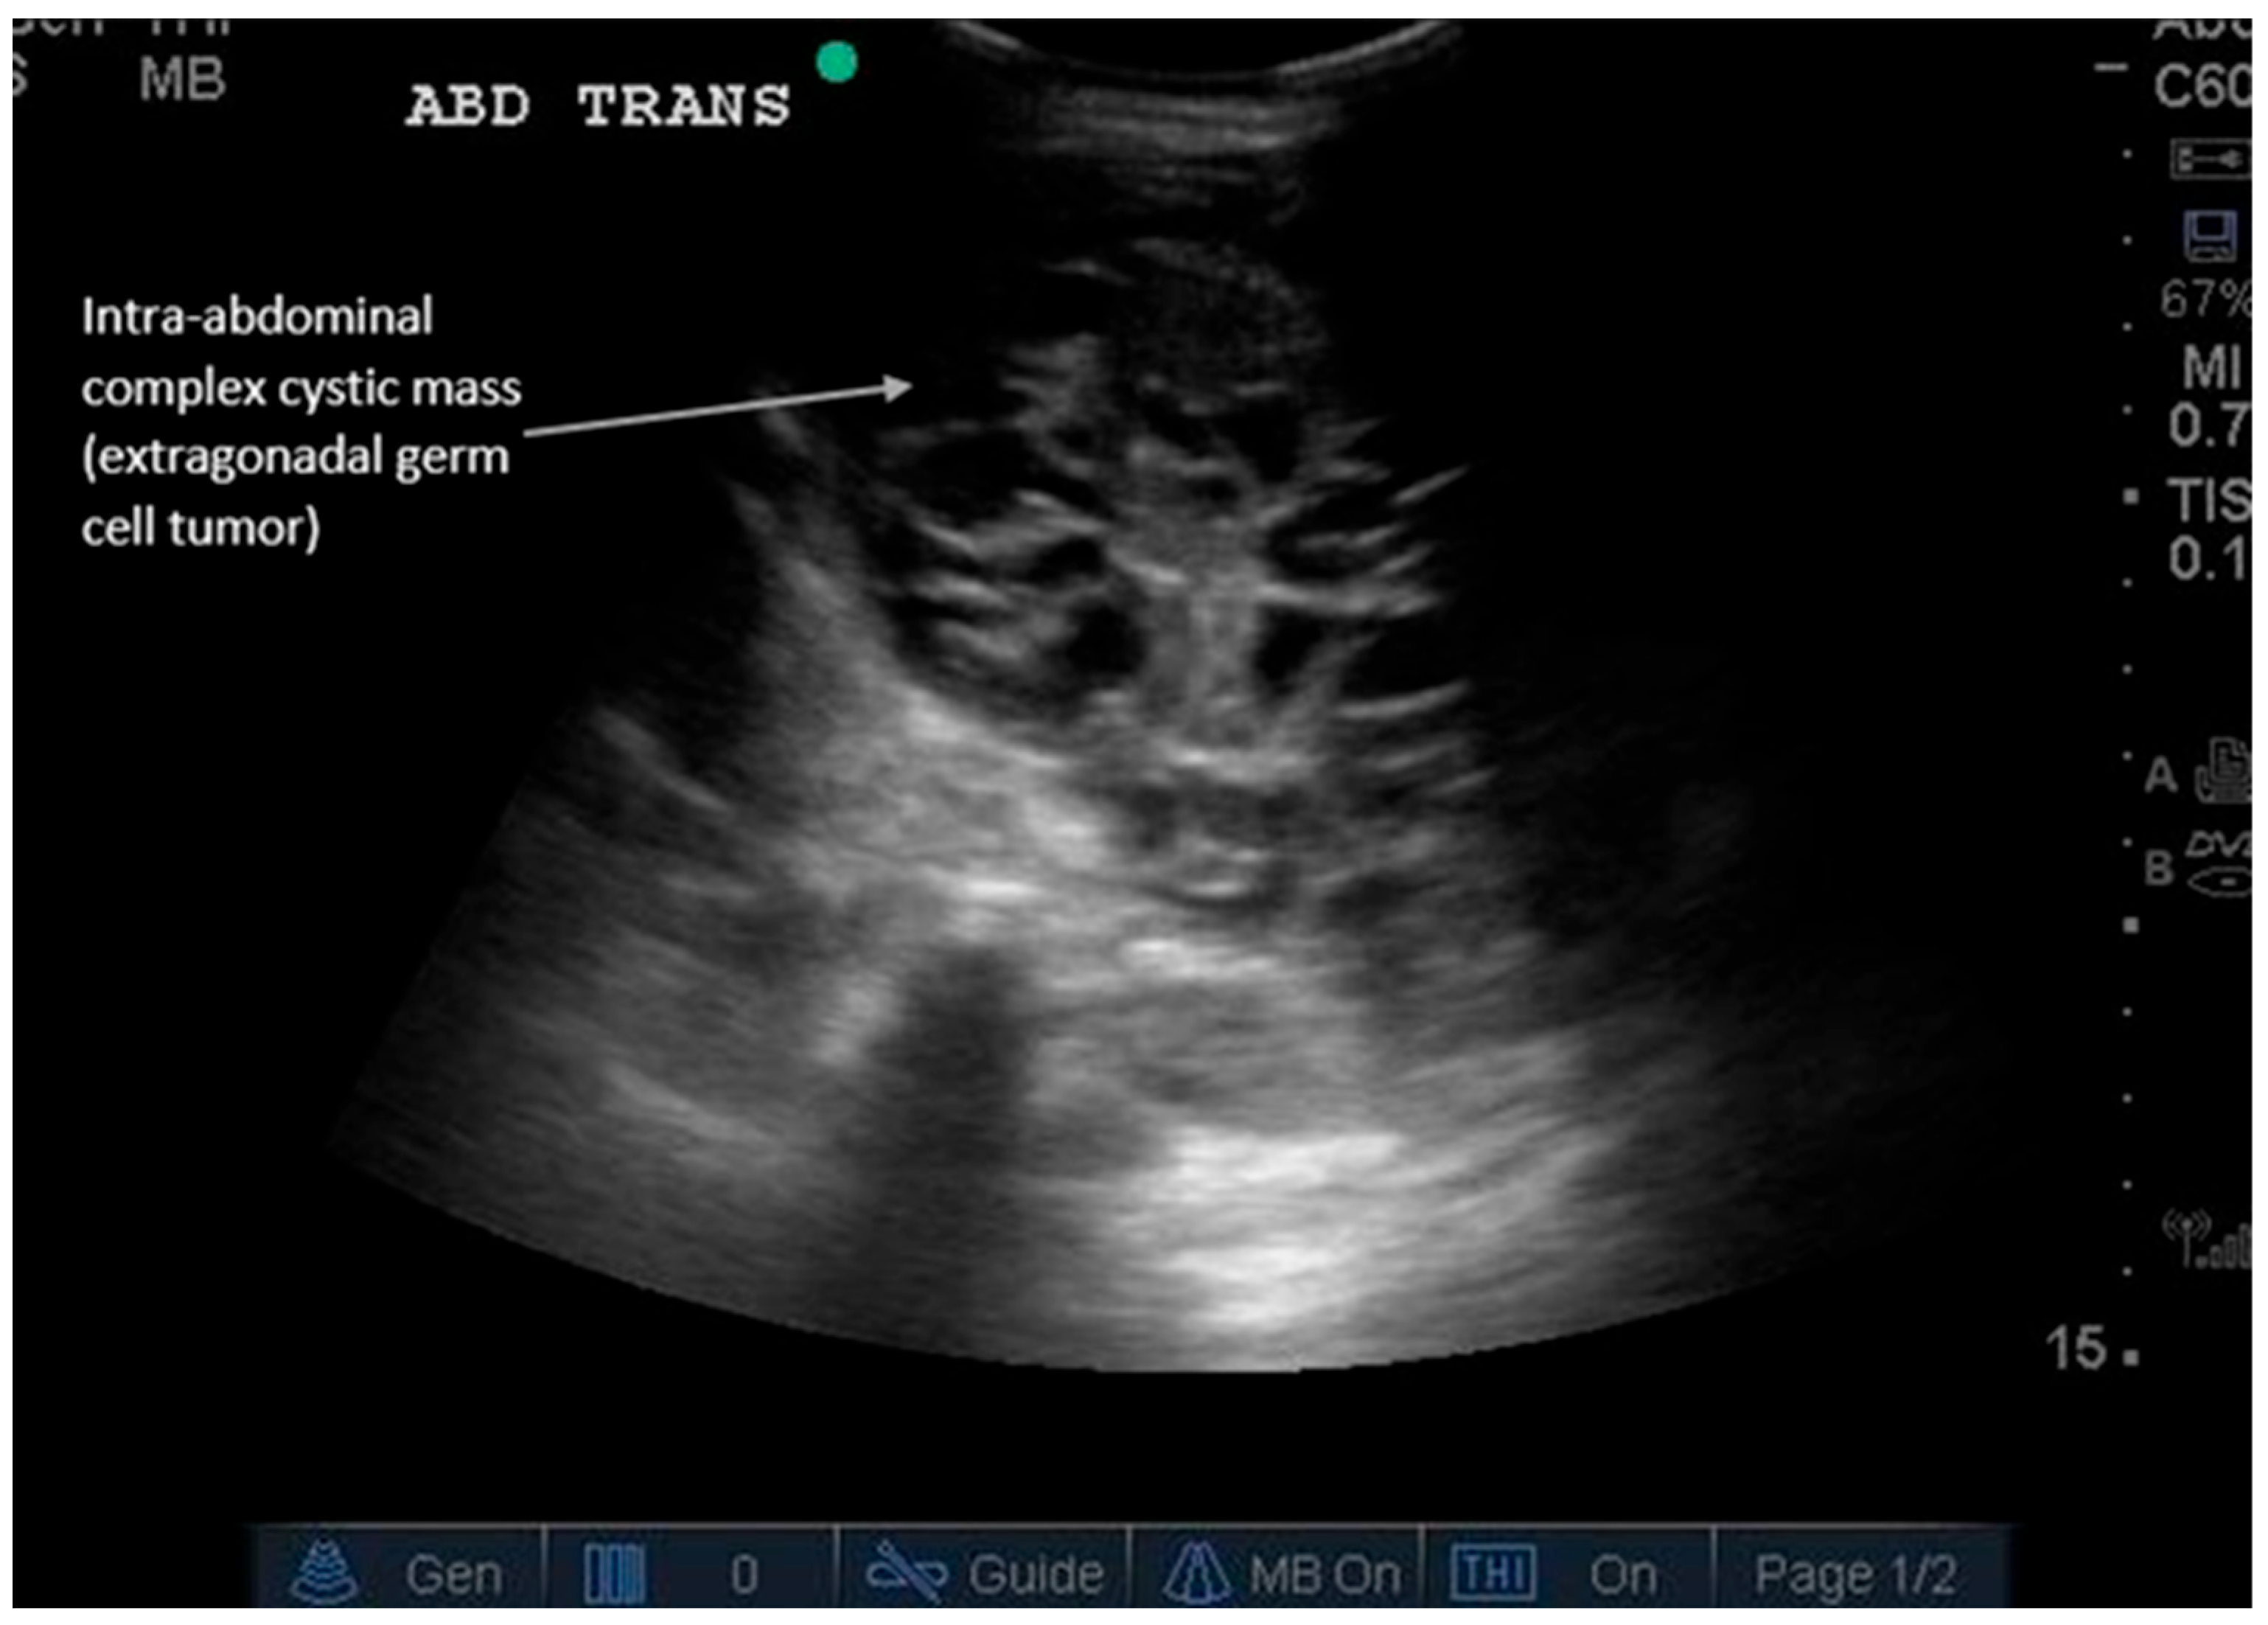

Figure 6.

Incidental abdominal mass. Abdominal masses can present differently depending on their internal composition. Ultrasound is the first-line modality for palpable masses because it can be performed at the site of palpation, determine echogenicity, and guide biopsy for definitive diagnosis. Supplementary Video S6 shows dynamic findings of an extragonadal germ cell tumor presenting as a complex, cystic intra-abdominal mass in an infant. Masses can be solid (hyperechoic), cystic (anechoic), or fatty (e.g., lipomas); simple or complex (can have septations); or can contain calcifications (1–2 mm small hyperechoic structures with posterior shadowing). Adding color Doppler can evaluate vascular flow within the mass (positive flow is more suggestive of malignancy). A round vs. irregular shape also helps determine whether it is benign or malignant, respectively. Ultrasound is particularly useful in pediatric abdominal masses to avoid radiation from CT scans and allow expedited diagnosis. Types of pediatric malignant masses include Wilms’ tumor (typically intrarenal), hepatoblastoma (liver), neuroblastoma, non-Hodgkin’s lymphoma, germ cell tumor (ovarian or testicular), and others [27]. Subsequent imaging for detected masses includes Magnetic Resonance Imaging (MRI) for indeterminate fat-containing or solid masses and CT for fluid collections after trauma or surgery or for suspected metastases requiring restaging imaging [18,27]. Supplemental Table S1 summarizes the major diagnostic findings for each GI pathology described and the recommended locations for POCUS scanning. Supplemental Table S2 describes the sensitivity and specificity of ultrasound compared to computed tomography (CT) for various gastrointestinal pathologies [13,14,15,18,19,20,21,24,26,27,28]. Conclusions: In summary, POCUS is a validated, guideline-endorsed tool for the rapid initial assessment of common GI pathologies. Its integration into clinical pathways for abdominal pain can improve diagnostic efficiency, reduce radiation exposure, and expedite definitive care.